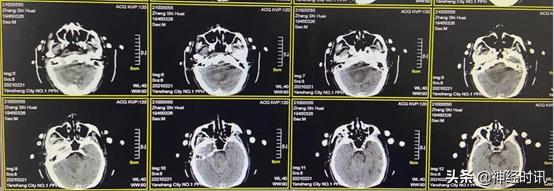

入院时急诊头颅CT检查提示小脑大量出血,量约30 ml,且破入脑室,脑干已受压,随时可能出现呼吸骤停,建议急诊手术清除小脑血肿,病情及手术相关风险向患者家属详细交代,其家属经过协商后拒绝手术,要求对症保守治疗。

入院时(1月18日),急诊头颅CT提示小脑出血约30 ml